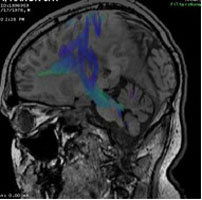

The UAB Department of Radiology at present has eight clinical MRI units, with construction in the University Hospital North Pavilion completed in the past year adding large bore 1.5 and 3T systems. An extremity MRI is conveniently located in the orthopedic clinics at UAB Highlands hospital. All MR machines have the full complement of coils, high performance gradients, and post processing capabilities in place to perform state of the art imaging including advanced diffusion weighted and diffusion tensor imaging, dynamic contrast enhanced and dynamic susceptibility enhanced MRI. Images sent from the Kirklin Clinic or University Hospital MRI suites to the 3D Laboratory for Multimodality Imaging for Patients, the MNIRC (Multidisciplinary NeuroImaging Resource Core) or CCQIBAD (Comprehensive Core for Quantitative Imaging Biomarker Analysis and Development) can be manipulated using TeraRecon, Dynasuite, StealthViz, Neuro IB platforms or study-specific software developed by UAB personnel.

Research MRI examinations are performed on the UAB Radiology Department's clinical magnets as well as on dedicated research units located in the Boshell Building and in the Civitan International Research Center. Advanced post processing of imaging data from all three resources may be additionally performed investigators in the MNIRC, CCQIBAD, or the Laboratory for Multimodality Imaging for Small Animals in the Division of Advanced Medical Imaging.

Recent growth areas include musculoskeletal and abdominal MRI, with 16% and 15% increases in volume, respectively, in FY2012. New capabilities with recent University Hospital Installation include full service functional MRI, as well as interventional breast procedures at 3T field strength.